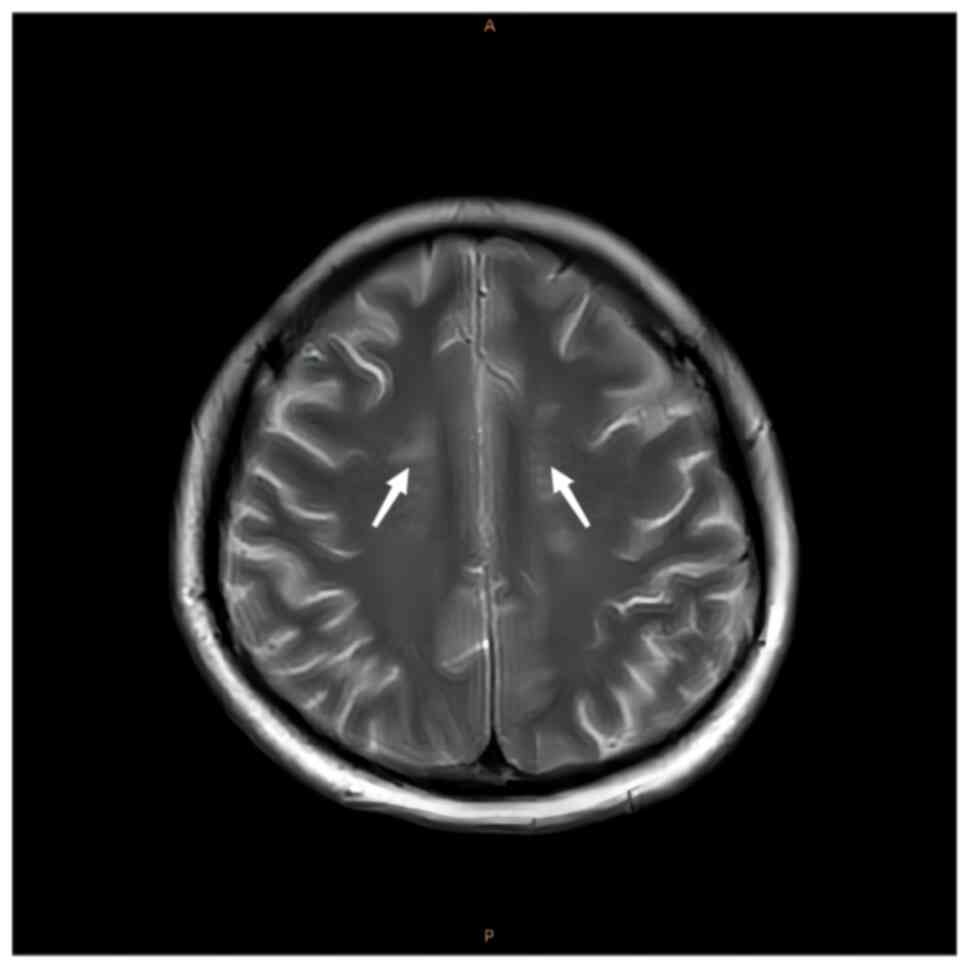

4). MRI of the brain demonstrated

spot-like and short-stripe abnormal signals that were distributed

symmetrically in the centrum semiovale, with equal or a slightly

low signal intensity on T1W1 and a slightly high signal intensity

on T2W1 (Fig. 5) and

While SCD rarely causes changes in the brain, in the

present study, the patient with SCD demonstrated abnormal changes

weakness, sensory ataxia and paraesthesia (11). In the present study, the patient's

lesions were mainly in the bilateral centrum semiovale as there was

a high signal in this region on T2 MRI and FLAIR. In the present

study, the lesions were symmetrical and perpendicular to the long

axis of the bilateral lateral ventricles, which is a characteristic

manifestation of SCD. These lesions are either directly or

indirectly related to the vitamin B12 deficiency observed in the

patient.